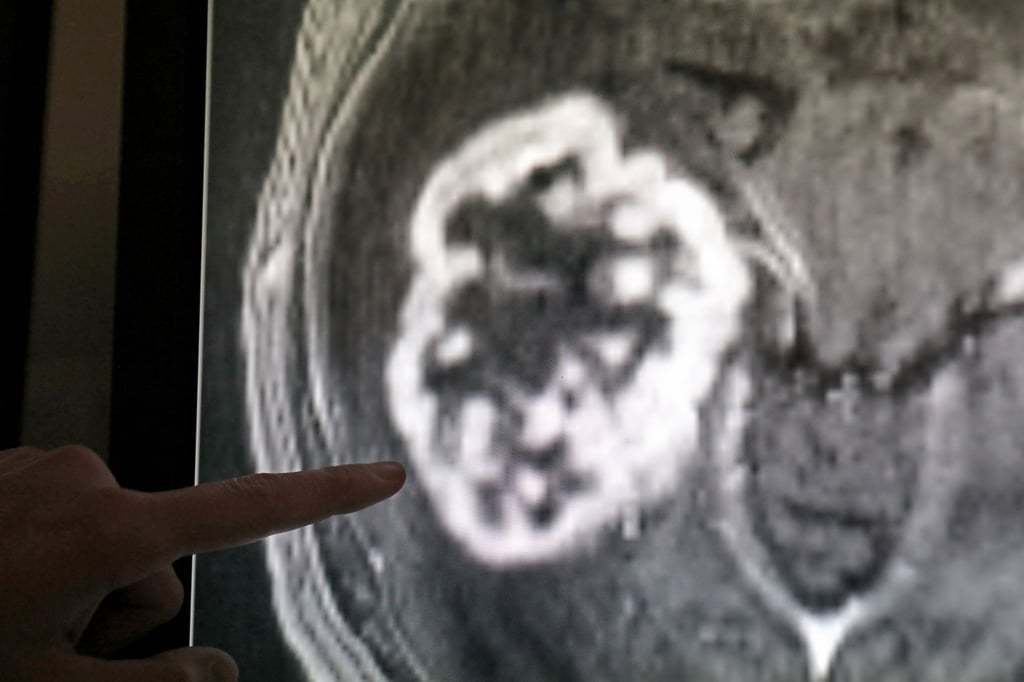

Den Statistikern zufolge lag das mittlere Sterbealter bei der Todesursache Krebs bei 74,4 Jahren – Männer starben im Schnitt 1,6 Jahre früher als Frauen (75,3 Jahre). Gut ein Drittel aller Krebstoten in Sachsen-Anhalt (2.716) starb den Angaben zufolge an Krebsleiden an Verdauungsorganen, etwa Darm-, Bauchspeicheldrüsen- und Magenkrebs. In 1.509 Fällen führte Lungenkrebs zum Tod, davon waren in 958 Fällen Männer betroffen.